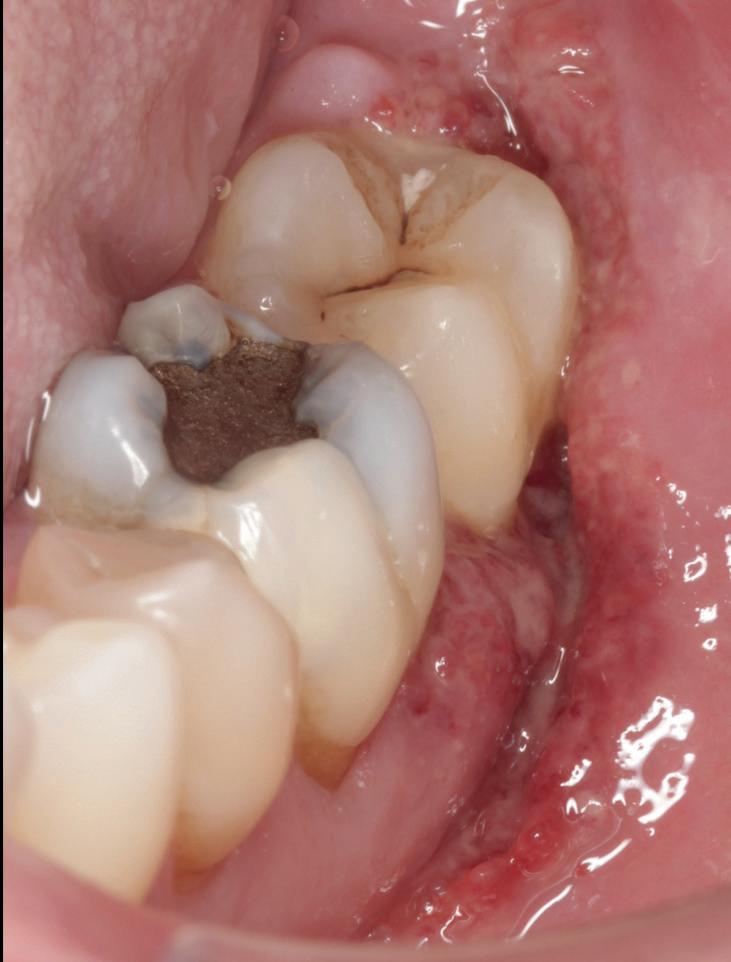

De patiënt werd in de eerste fase gezien door de parodontoloog, implantoloog en restauratief behandelaar. Klinisch werden drie complicerende factoren vastgesteld: inadequate mondhygiëne, een ongunstige occlusale relatie en restauraties met gebrekkige marginale adaptatie met overhang. De patiënt werd opgenomen in het parodontale behandelprotocol.

De diagnose luidde lokaal parodontitis met ernstige furcatie aandoeningen; Stadium IV (vergevorderd); graad C (snel progressief) (afbeelding 7) De elementen die niet te behouden waren, werden geëxtraheerd.

Na afronding van de eerste twee behandelstappen werd parodontale stabiliteit bereikt, zoals waarneembaar op de parodontiumstatus en (röntgen)foto’s (afbeelding 6, 8). De patiënt toonde aantoonbare verbetering in mondhygiëne (afbeelding 4) en bleef gemotiveerd om de behandeling voort te zetten.